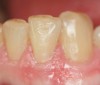

A critical filler size is 1 µm. Fillers greater than 1 µm are visible to the eye.21 As resin matrix around filler particles wears, fillers become prominent and visible, resulting in a composite surface that appears rough. As a result, a filling can seem smooth after placement and polishing, only to appear rough a year later. However, fillers less than 1 µm do not produce this rough surface effect with age. Case 4 shows restoration of peg laterals following orthodontic treatment in an 18-year-old female, using a micro hybrid composite (Figure 10 and Figure 11).

Figure 10  Retracted teeth showing peg lateral.

Figure 10

Figure 11  Retracted teeth showing restoration of peg laterals.

Figure 11